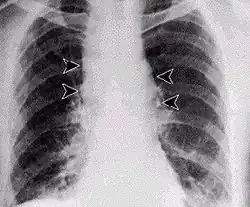

Inhalation anthrax usually develops within a week after exposure, but may take up to 2 months.[28] During the first few days of illness, most people have fever, chills, and fatigue.[28] These symptoms may be accompanied by cough, shortness of breath, chest pain, and nausea or vomiting, making inhalation anthrax difficult to distinguish from influenza and community-acquired pneumonia.[28] This is often described as the prodromal period.[28]

Over the next day or so, shortness of breath, cough, and chest pain become more common, and complaints not involving the chest such as nausea, vomiting, altered mental status, sweats, and headache develop in one-third or more of people.[28] Upper respiratory tract symptoms occur in only a quarter of people, and muscle pains are rare.[28] Altered mental status or shortness of breath generally brings people to healthcare and marks the fulminant phase of illness.[28]

It infects the lymph nodes in the chest first, rather than the lungs themselves, a condition called hemorrhagic mediastinitis, causing bloody fluid to accumulate in the chest cavity, thereby causing shortness of breath. The second (pneumonia) stage occurs when the infection spreads from the lymph nodes to the lungs. Symptoms of the second stage develop suddenly within hours or days after the first stage. Symptoms include high fever, extreme shortness of breath, shock, and rapid death within 48 hours in fatal cases.[29]